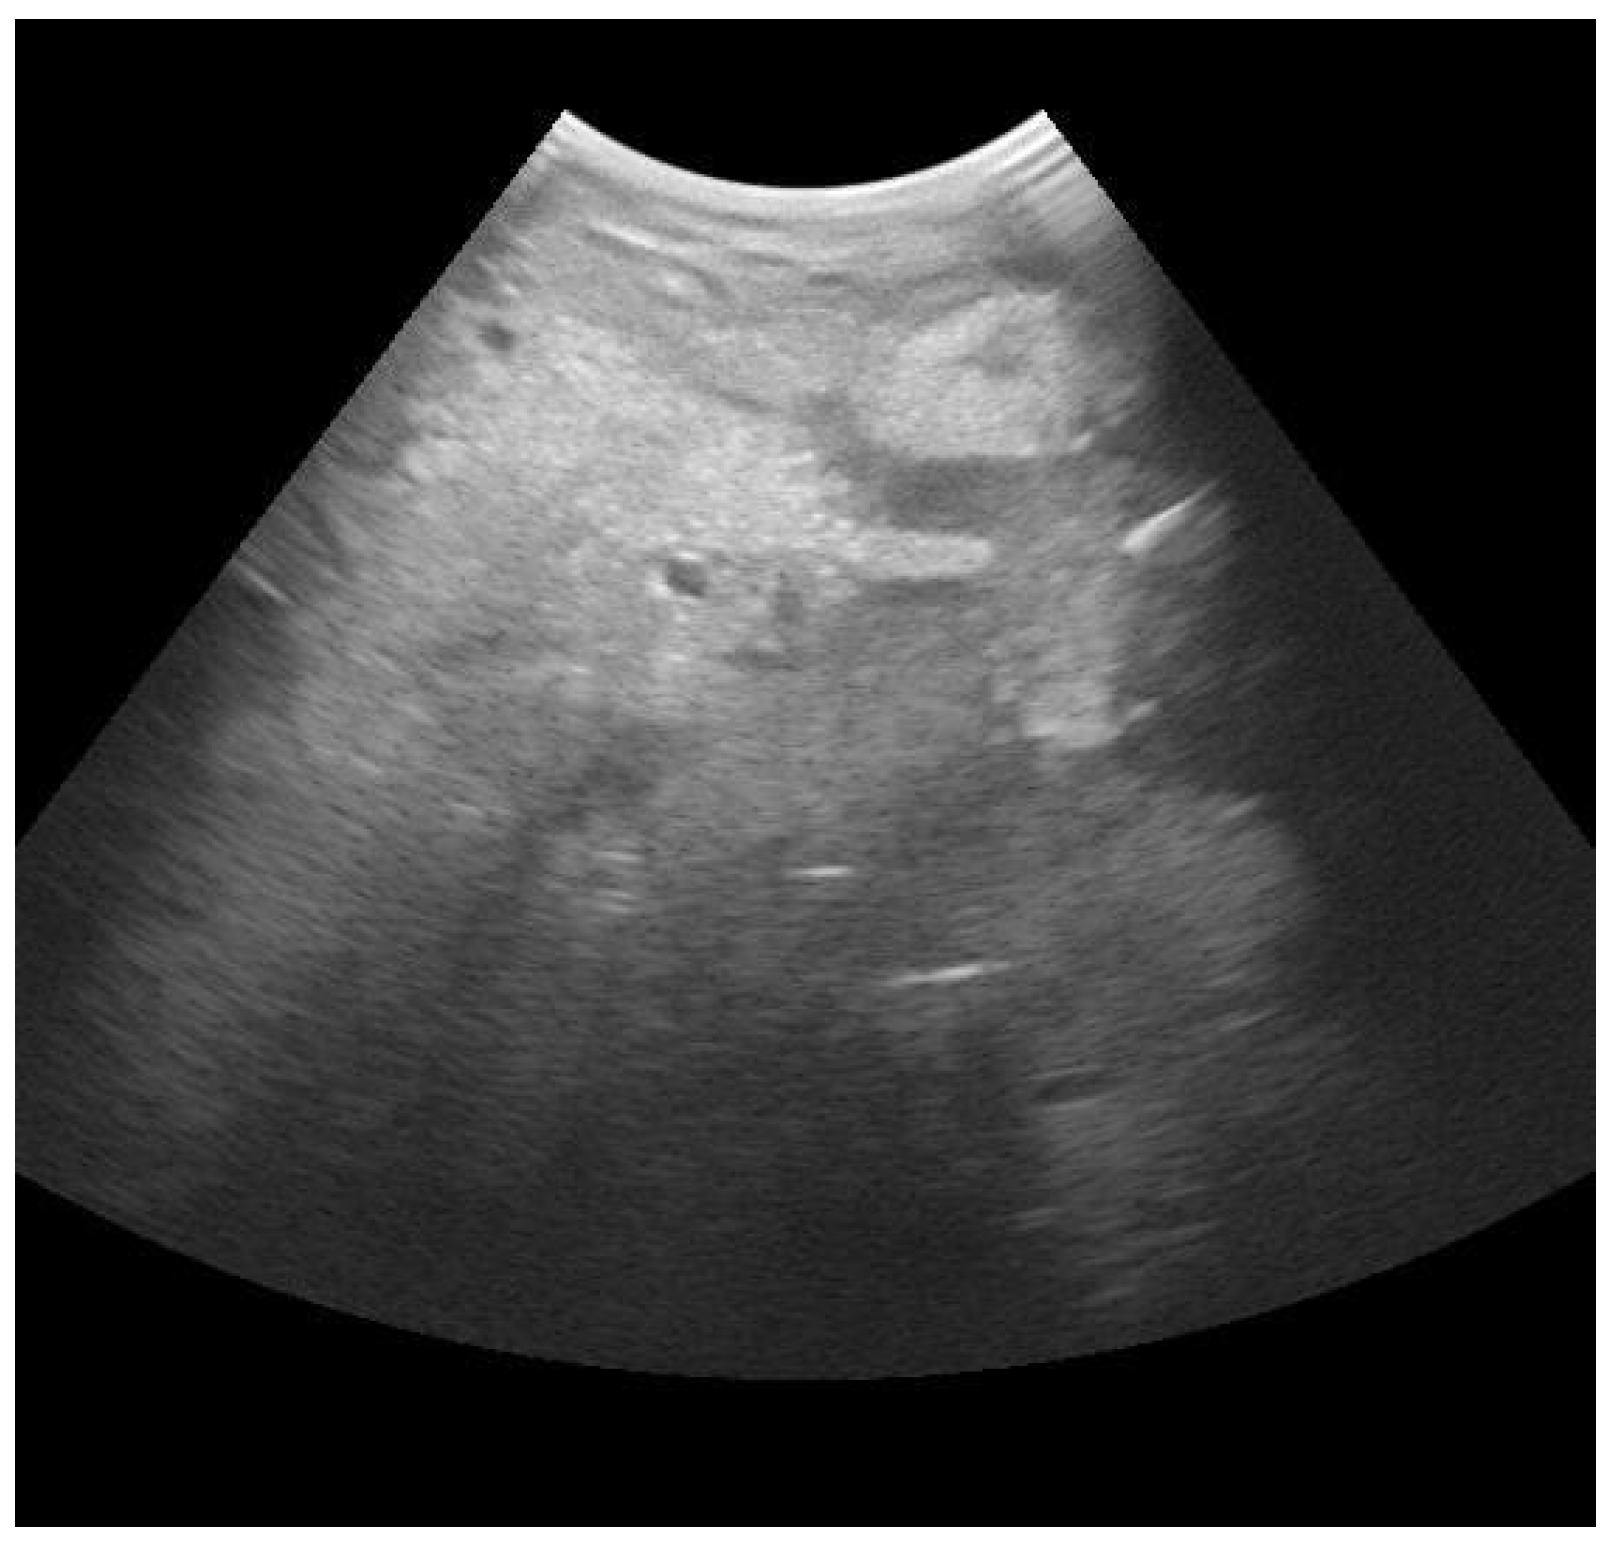

- Suzuki, N.; Kurose, T.; Kaneko, S.; Haraguchi, A.; Isobe, N. Outcome Prediction from the First Examination in Clinical Mastitis Using Ultrasonography in Dairy Cows. Anim. Sci. J. 2020, 91, e13452. [Google Scholar] [CrossRef] [PubMed]

- Aishwarya Sunder, H.; Gupta, D.; Singh, R.; Singh, S.; Randhawa, C. Ultrasonographic Changes in Teat and Supramammary Lymph Nodes in Dairy Cows Affected with Clinical Mastitis. Haryana Vet. 2022, 61, 68–71. [Google Scholar]

- Flöck, M.; Winter, P. Diagnostic Ultrasonography in Cattle with Diseases of the Mammary Gland. Vet. J. 2006, 171, 314–321. [Google Scholar] [CrossRef]

- Mourya, A.; Shukla, P.C.; Gupta, D.K.; Sharma, R.K.; Nayak, A.; Tiwari, A.; Singh, B.; Singh, A.P.; Sahi, A.; Jain, A. Ultrasonographic Alteration in Subclinical Mastitis in Cows. J. Entomol. Zool. Stud. 2020, 8, 2058–2063. [Google Scholar]